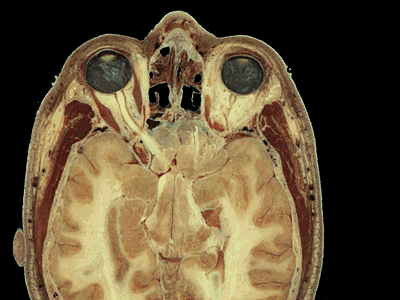

Because students are asked to identify some of the smaller vessels and nerves on each image, the program includes a zoom-in feature. A right mouse click calls up the enlarged view that allows the student to see the image at higher resolution. A left mouse click then returns the student to the interactive view.